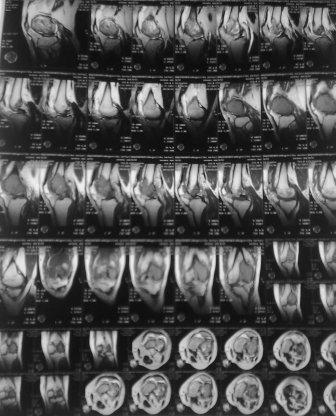

Обратился мужчина 32 лет с жалобами на боли в обл. внутреннего мышелка левого бедра. Боли беспокоят около шести месяцев, лечился дома всякими мазями и т.д. 2 неделя назад упал , и после этого боли с каждым днем усиливаются. Местно определяется резкая болезненность в обл. мышелка бедра, явление не выраженного синовита, ограничение движения в коленном суставе, мягкотканый компонент опухоли не определяется, лимфоузлы не увеличены,Р-скопия легких без патологии,клинико-биохимические анализы в пределах нормы. Гистология- гигантоклеточная опухоль.

Направил в онкологический центр, рекомендовали резекцию и ревизионное эндопротезирование коленного сустава, от которого больной отказался и опять вернулся к нам, временно фиксировали гипсовой повязкой.

Уважаемые коллеги можно ли помочь больному, т.к. на практике были, что после перелома опухоль рассосалась и переломы срослись! Или может быть аутопластика и фиксация перелома?